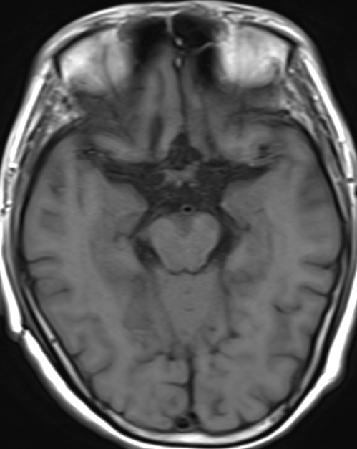

2013-8-2 MRI

2013-8-2 CT

腰穿脑压240